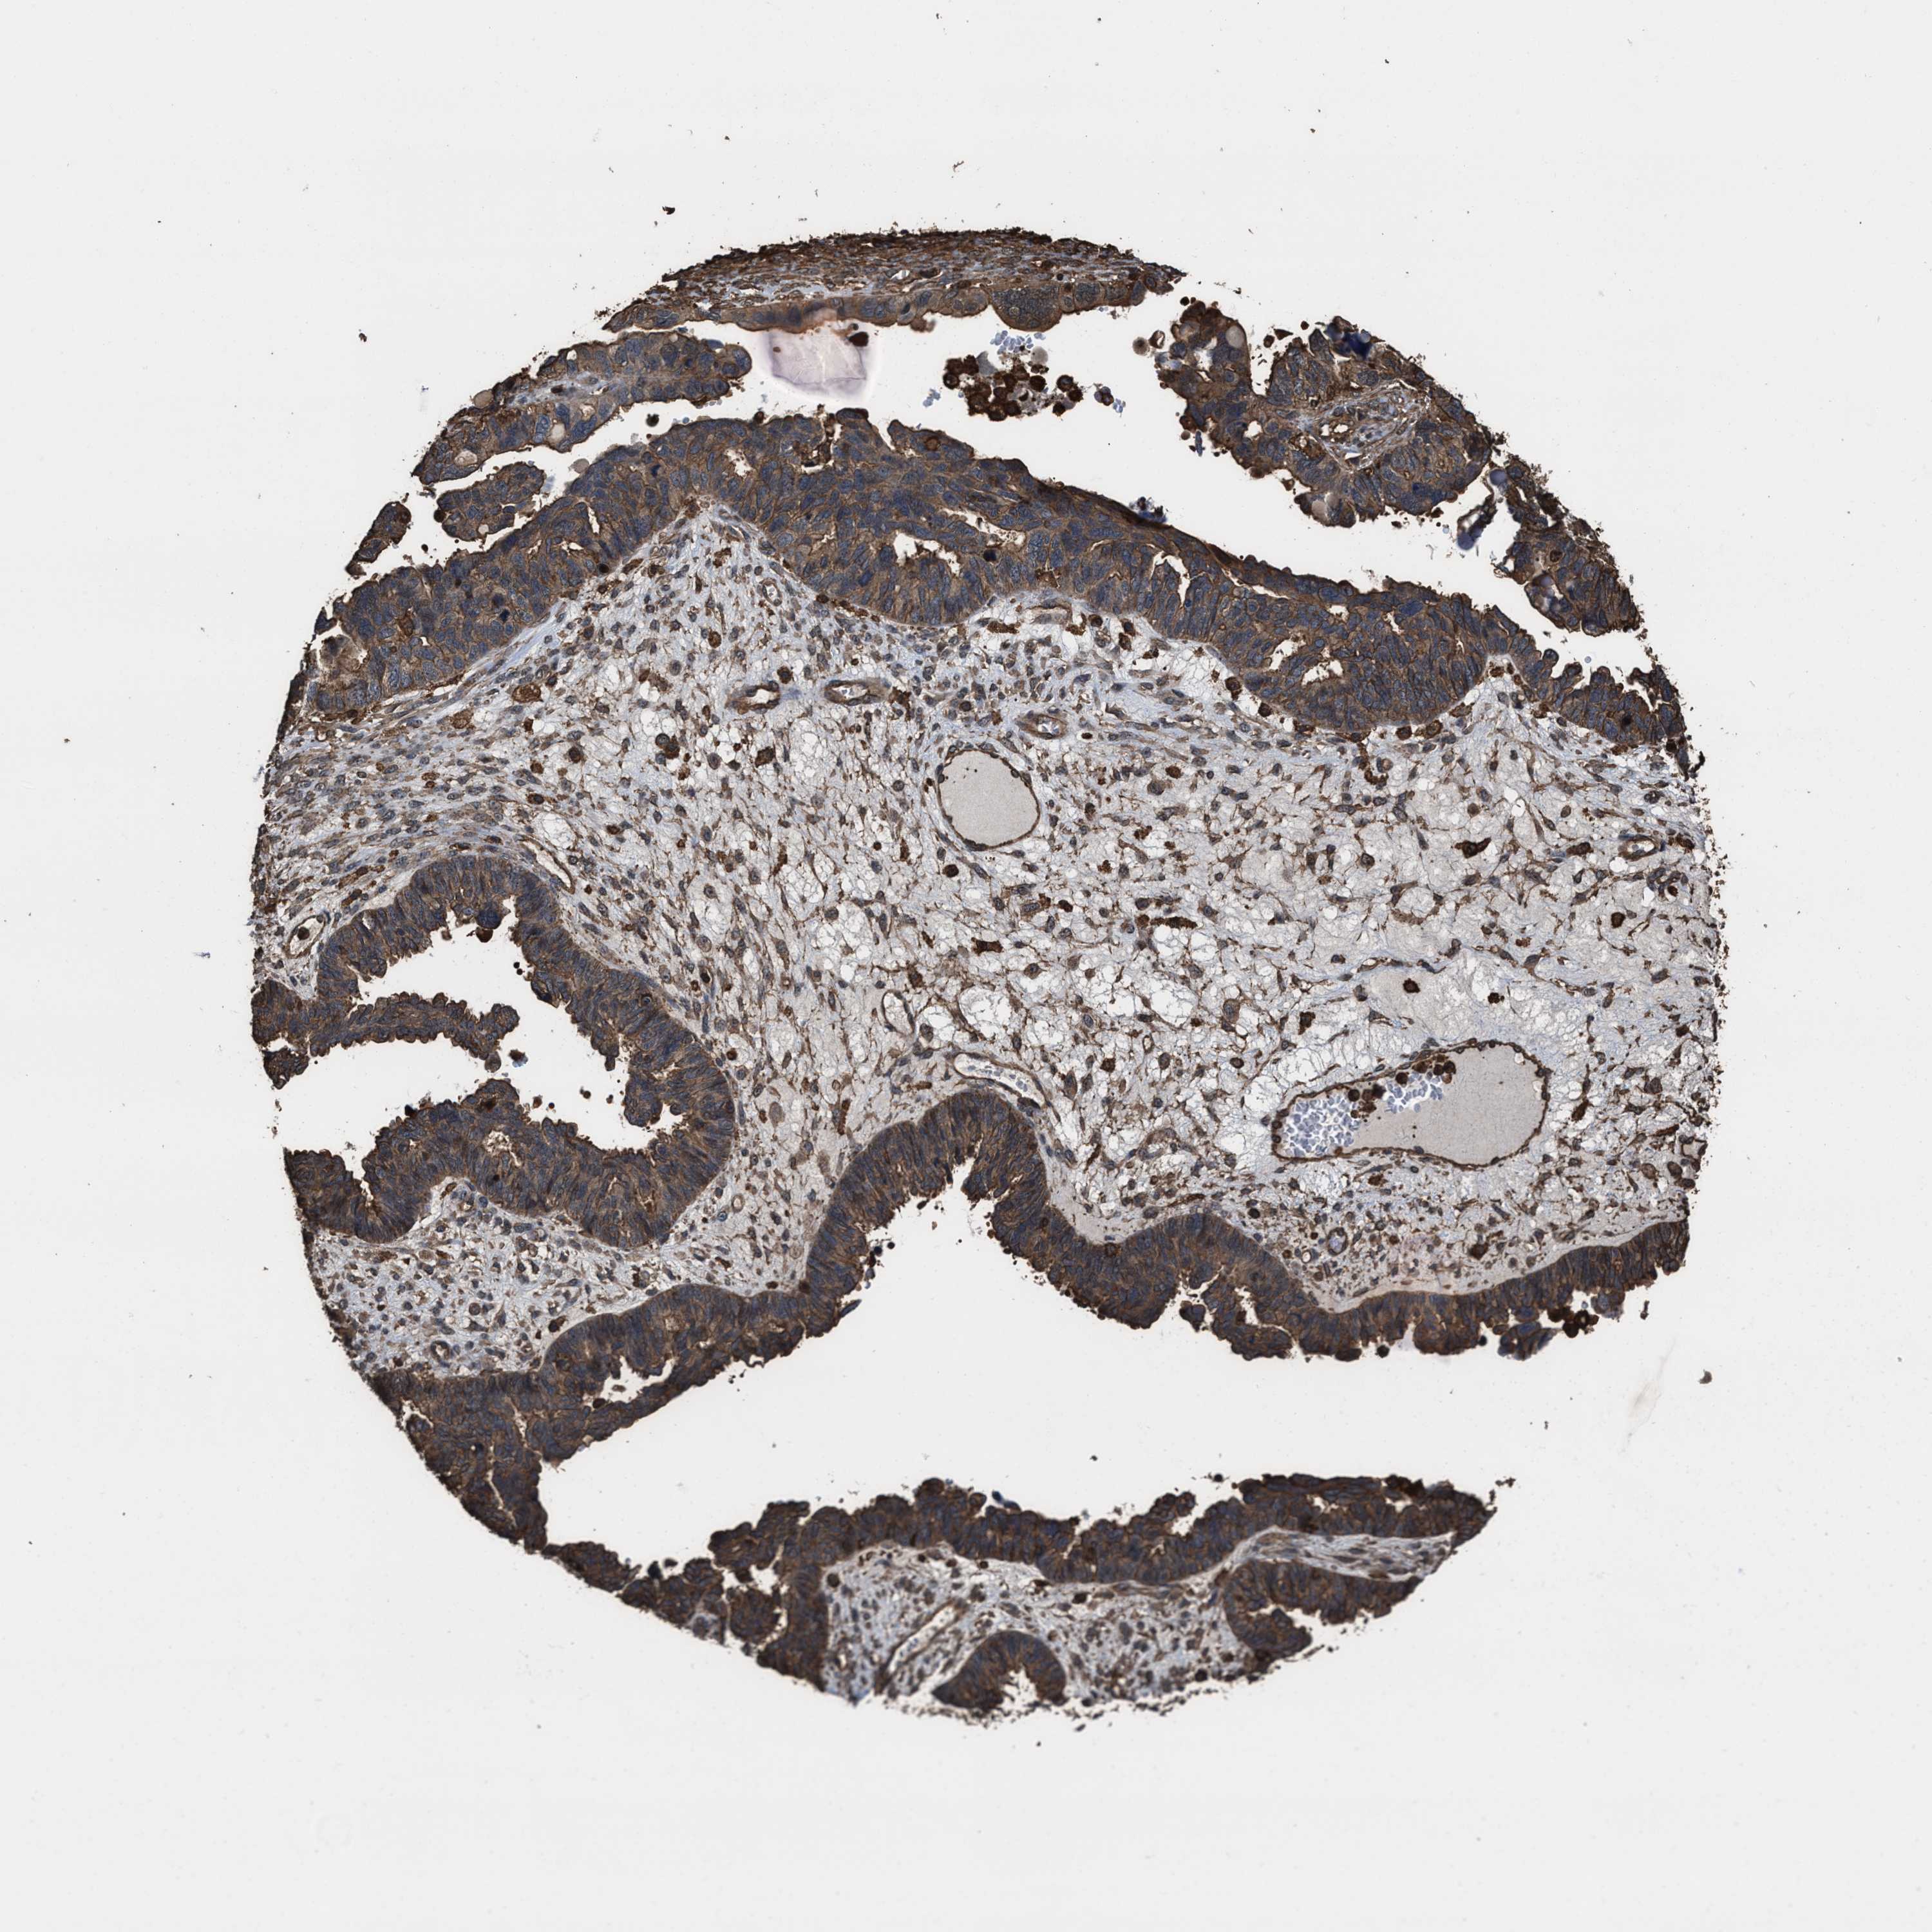

OVARIAN CANCER - Protein expressioni

A mouse-over function shows sample information and annotation data. Click on an image to view it in a full screen mode. Samples can be filtered based on level of antibody staining by selecting one or several of the following categories: high, medium, low and not detected. The assay and annotation is described here.

Note that samples used for immunohistochemistry by the Human Protein Atlas do not correspond to samples in the TCGA dataset.

Antibody stainingi

Antibody staining in the annotated cell types in the current human tissue is reported as not detected, low, medium, or high, based on conventional immunohistochemistry profiling in selected tissues. This score is based on the combination of the staining intensity and fraction of stained cells.

Each image is clickable and will lead to virtual microscopy that enables deeper exploration of all samples and also displays staining intensity scores, fraction scores and subcellular localization as well as patient and tissue information for each sample.

Antibody HPA021133

Cystadenocarcinoma, serous, NOS

Carcinoma, endometroid

Cystadenocarcinoma, mucinous, NOS

Carcinoma, NOS